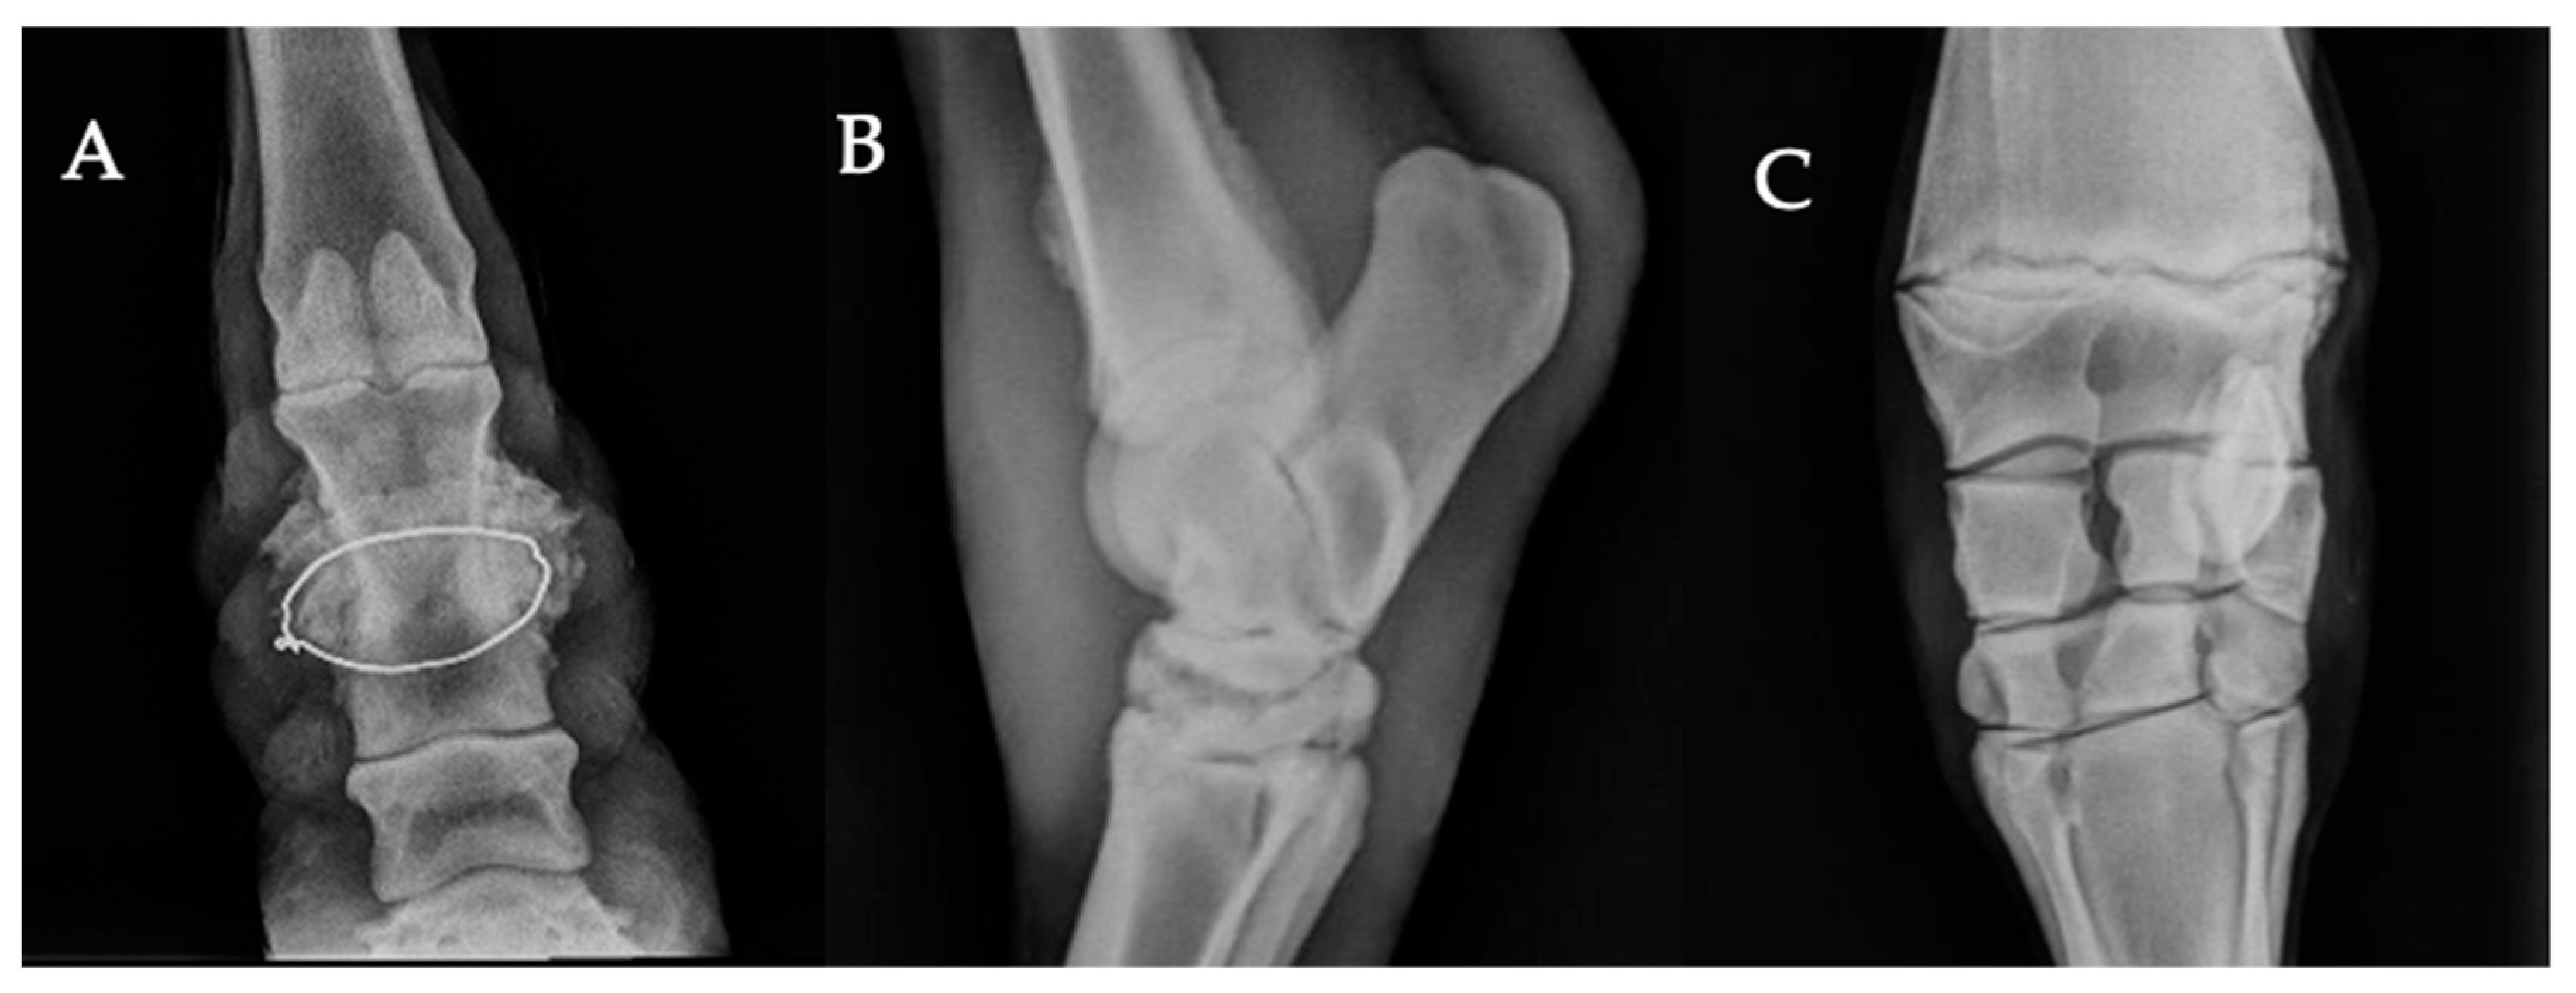

- Degenerative joint disease (DJD). Included radiographic evidence of periarticular osteophytes or enthesophytes, subchondral sclerosis, narrowing or collapse of the joint space, with or without partial ankylosis.

- Epiphyseal conditions. Included developmental abnormalities of the growth plate, such as incomplete ossification, physeal irregularities, and metaphyseal flaring in young animals.